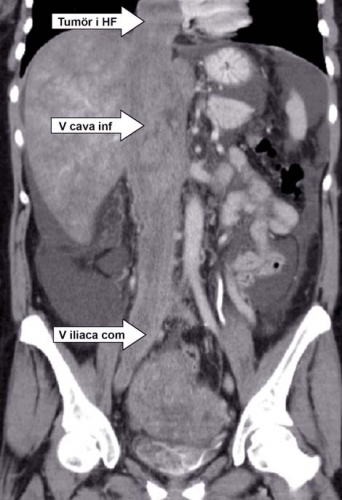

Patienten försämrades dock med tilltagande kraftig leversvikt; ny datortomografi verifierade leverstas och ascites. Det som tidigare uppfattats som en vena cava-trombos bedömdes nu som en heterogen tumörmassa (Figur 1), vilken också omfattade uterusområdet. Den tumörsuspekta tromben fyllde ut hela vena cava inferior och sträckte sig in i höger förmak (Figur 2).